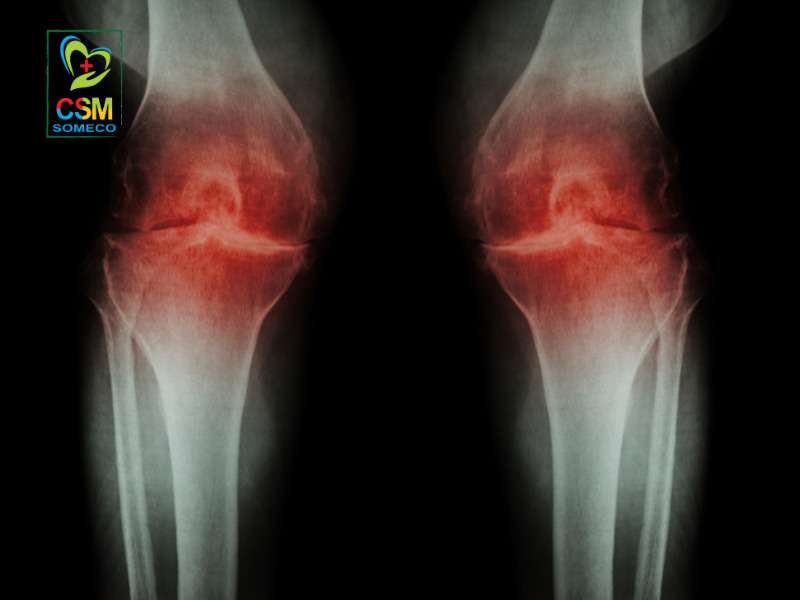

Viêm xương khớp là bệnh lý mạn tính làm tổn thương toàn bộ cấu trúc khớp. Bệnh đặc trưng bởi sự phá hủy sụn khớp và những thay đổi ở xương dưới sụn. Đây đang là một vấn đề y tế công cộng mang tính toàn cầu.

Viêm xương khớp là bệnh lý mạn tính làm tổn thương toàn bộ cấu trúc khớp, đặc trưng bởi sự phá hủy dần lớp sụn (lớp đệm đàn hồi) bao bọc đầu xương. Khi lớp sụn này bị bào mòn, các đầu xương sẽ cọ xát trực tiếp vào nhau, gây ra các triệu chứng điển hình như đau, sưng, cứng khớp và theo thời gian có thể hình thành gai xương, làm biến dạng khớp và hạn chế khả năng vận động.